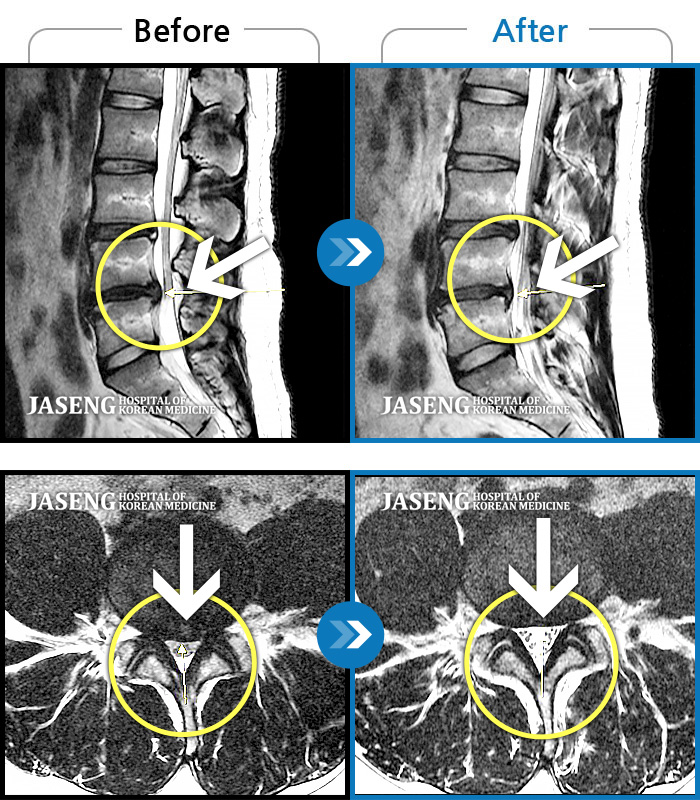

Before

After

환자에게 사전 동의를 받아 동일 조건에서 촬영되었습니다.

개인에 따라 치료 후 부작용이 발생할 수 있으니 의료진과 상담 후 치료를 진행하시기 바랍니다.

요추 4번과 요추 5번 사이에서 탈출된 디스크가 신경막을 압박

허리 통증, 야간통으로 내원